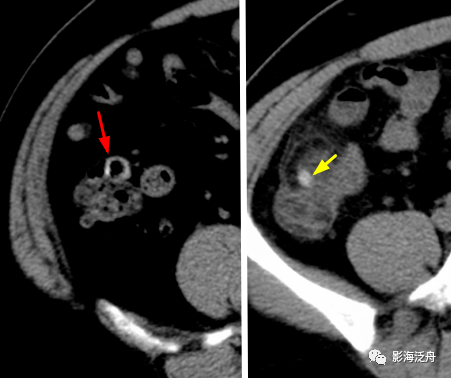

盲肠前壁的憩室炎,憩室内含高密度粪石影(红箭头),离憩室最近的地方即

阑尾根部(黄箭)稍增粗,壁厚而强化,近端管腔内见高密度粪石影,注意